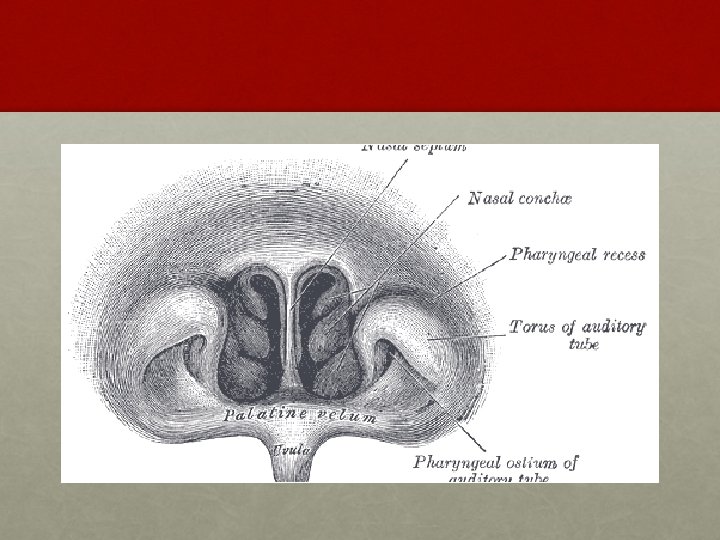

ANATOMY OF NASOPHARYNX • It opens anteriorly into the nasal cavity.